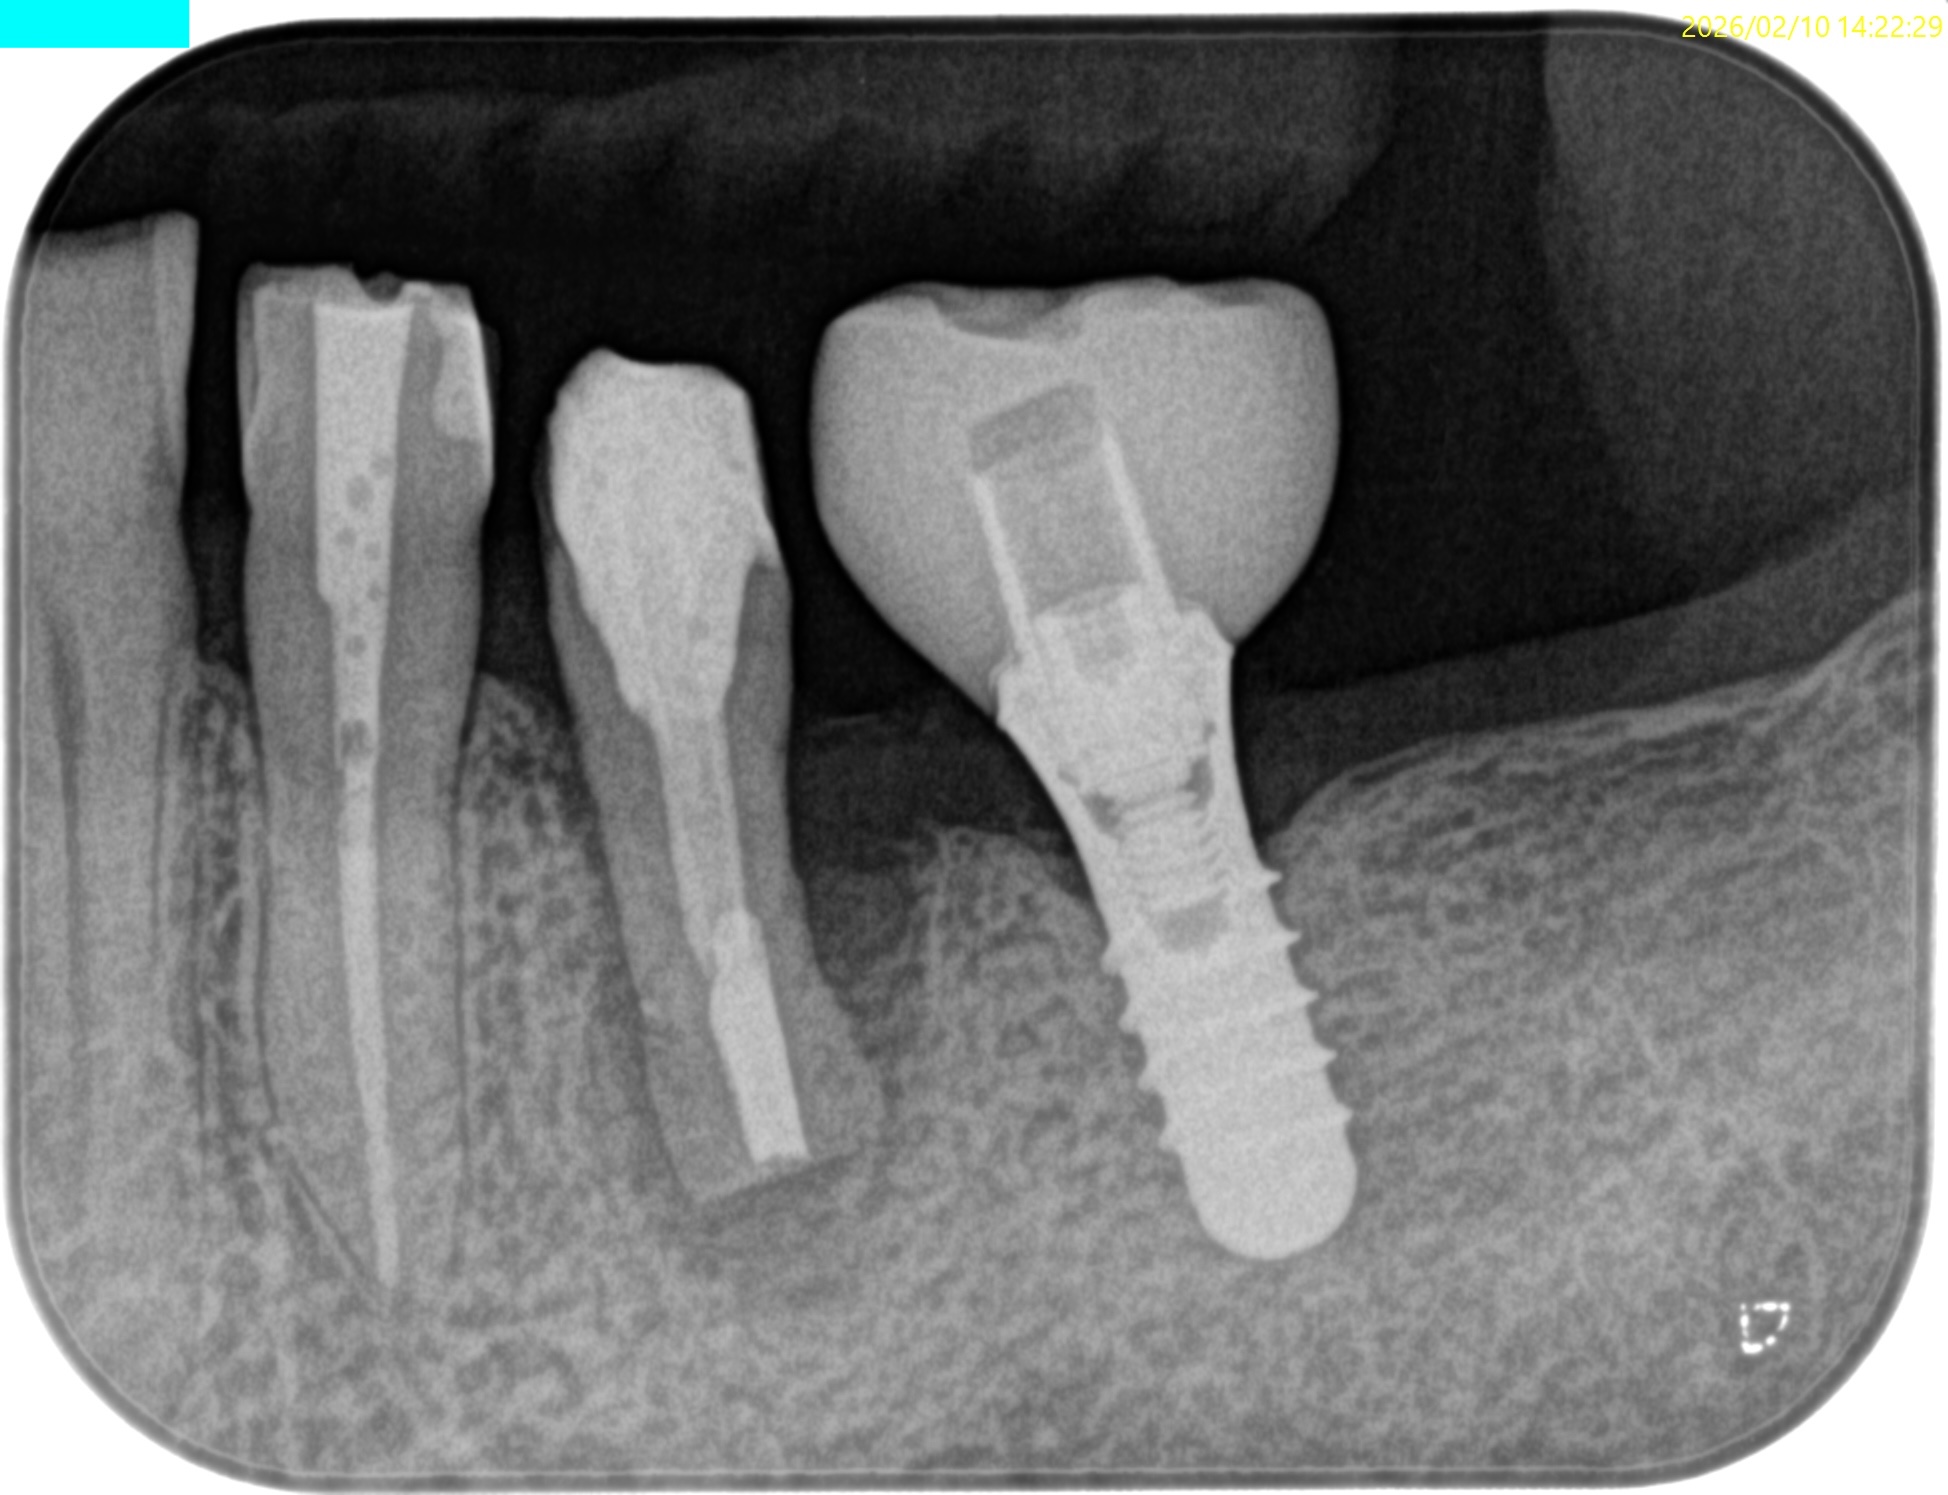

術後にPA, CBCTを撮影した。

長いスクリューピンの除去には約50分かかったがIntentional Replantationは15分で終了した。